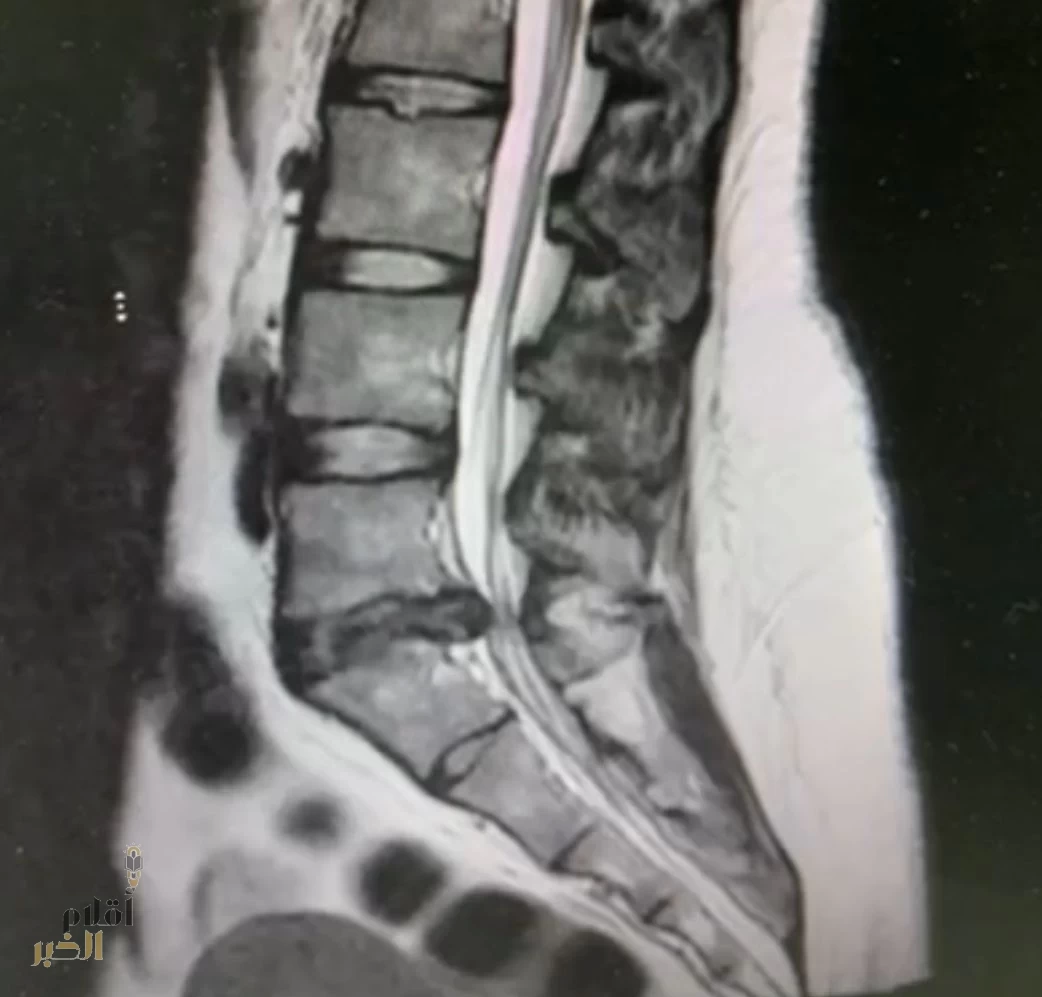

وبعد إجراء الفحوصات اللازمة، تبيّن وجود انزلاق غضروفي بين الفقرة القَطنية الخامسة والعَجُزية الأولى.

وقرر الفريق الطبي إجراء عملية جراحية بعد أن فشلت المسكنات والعلاج الطبيعي في النتائج المرجوة في تخفيف الألم، وبعد تنويم المريضة أُجريت لها عملية إزالة الغضروف الضاغط على الأعصاب باستخدام تقنية التدخل المحدود بالمنظار، عبر فتحة جراحية صغيرة لا تتجاوز 2 سم، وخرجت المريضة من المستشفى بعد يوم واحد من العملية وهي في حالة صحية جيدة.